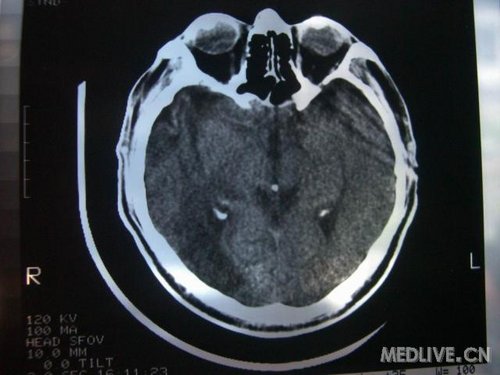

病人男性 73岁 市民 以“幻听、幻视两天,言语含糊、精神错乱一天”入院。

两天前无诱因出现幻听、幻视,描素眼前有彩色的圆圈,听见有人说话(但说什么不详),一天前出现胡言乱语,言语含糊,精神错乱,问话不答,行走略有不稳,来我院就诊,门诊头CT检查:(下面有片)入院后查体不合作,表情淡漠,问话不答,大致检查了一下,颅神经未见明显异常,颈软,右手活动似忽略差。其他检查不配合。脑电图:广泛轻-中度异常。

既往史:半年前曾患“右侧脑梗塞”但无明显后遗症,生活能自理,无高血压、糖尿病、心脏病史。

此次入院时的片子: